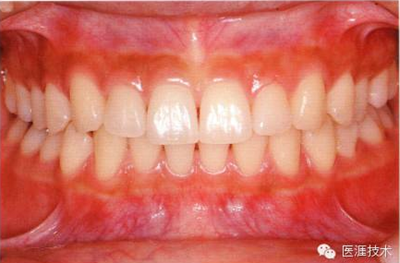

健康、正常的牙周組織如何形成?

健康牙周組織的牙齦邊緣呈珊瑚粉,邊緣牙齦略呈圓弧狀。牙間可見三角形的牙間乳頭,牙齦邊緣相連呈貝殼形。

附著齦與游離齦相連時,有時有游離齦溝存在(成人的30~40%)。

附著齦通過膠原纖維牢固結(jié)合骨骼與牙骨質(zhì),因此可見不可動、硬而緊繃的點彩(橘皮樣點狀凹凸)。

從牙齦牙槽粘膜到根尖有牙槽粘膜。牙槽粘膜為暗紅色,與骨骼結(jié)合較松,故可動。

健康且正常的牙周組織臨床圖像